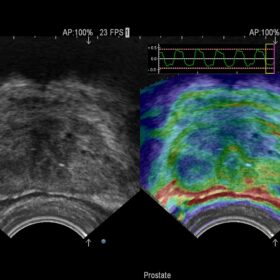

Radiology 2D, Color, Contrast and Elasto mode

- In radiology, a high-level of accuracy and reliability is necessary to ensure early detection, precise diagnosis, and to determine appropriate treatment. The ARIETTA V70* is equipped with advanced technologies that facilitate fast and accurate examinations. Such as Real-time Virtual Sonography (RVS), Real-Time Tissue Elastography and Shear Wave measurement.